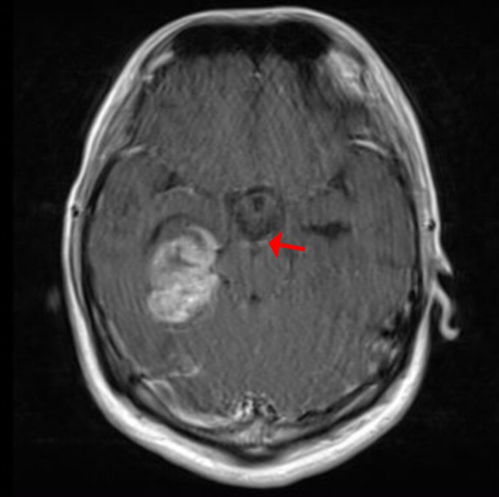

1. 影像学评估

通过CT或MRI等影像学检查,我们可以更直观地了解肿瘤的变化。完全缓解(CR)意味着肿瘤病灶完全消失并持续至少1个月;部分缓解(PR)则表示肿瘤最大直径缩小超过30%;而稳定(SD)则需要结合其他指标进行综合判断。